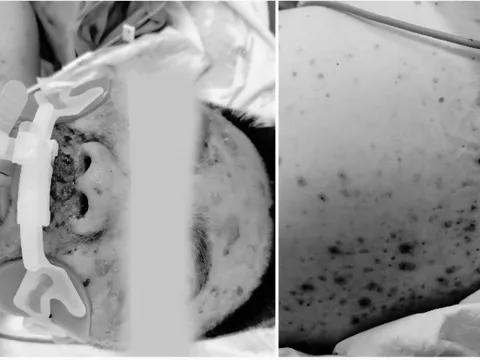

Theo thông tin từ Bệnh viện Bệnh Nhiệt đới Trung ương, tuần qua, nhiều ca bệnh có lịch sử du lịch hoặc làm việc tại các quốc gia thuộc châu Phi nhập viện với triệu chứng sốt cao, rét run, được chẩn đoán mắc sốt rét ác tính.